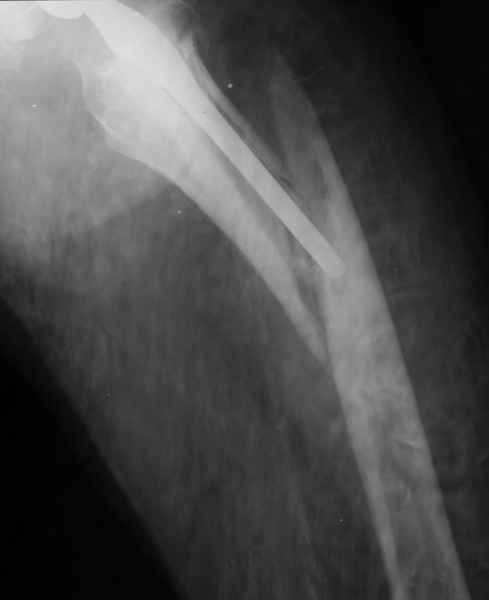

1.Остеосинтез на ножке. Мне кажется, что применительно к этому случаю малоперспективный вариант. Синтез хорош, когда можно его выполнить в малоинвазивном исполнении и достигнуть стабильности. Действительно, если ножка б/цементной фиксации после этого не будет иметь фиксации, то ревизия не будет иметь проблем. В представленном случае стабильность синтеза сомнительная, а проведение доп.иммобилизации приведет к контрактуре суставов.

Хочется показать два подобных случая, П-ка З. 72 лет и п-т Г. 80 лет. Сразу принимаю замечание, что это были ножки цементной фиксации, просто под руками не было бесцементника.